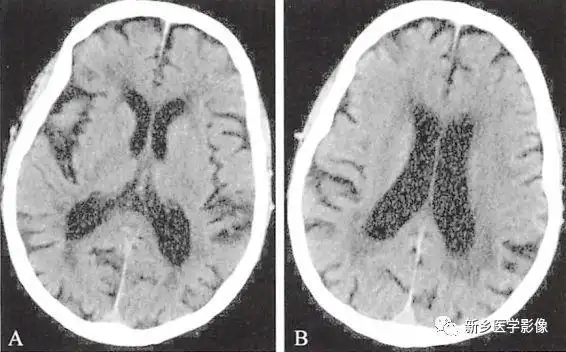

两种常见脑萎缩ct表现

庄xx脑萎缩治疗前后映像对比图 - 山东潍坊吉缘堂抗衰老中医药研究所